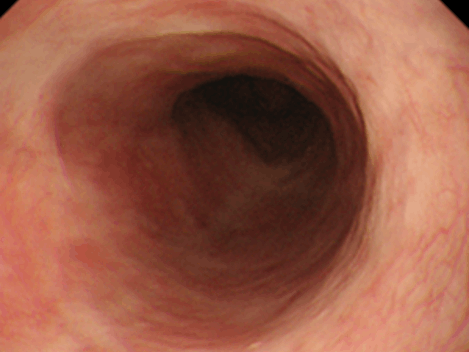

投薬治療でわずかな縦走溝・軽度白斑の状態に改善。消化管からの血液は粘膜で吸収された栄養素を多く含んでいるため、そのほとんどは門脈を介して肝臓へといたります。そして肝臓は、これを代謝して体に必要な形に変えたり、有害な成分を無毒化したり、栄養を蓄えたりするという役割を担っています。